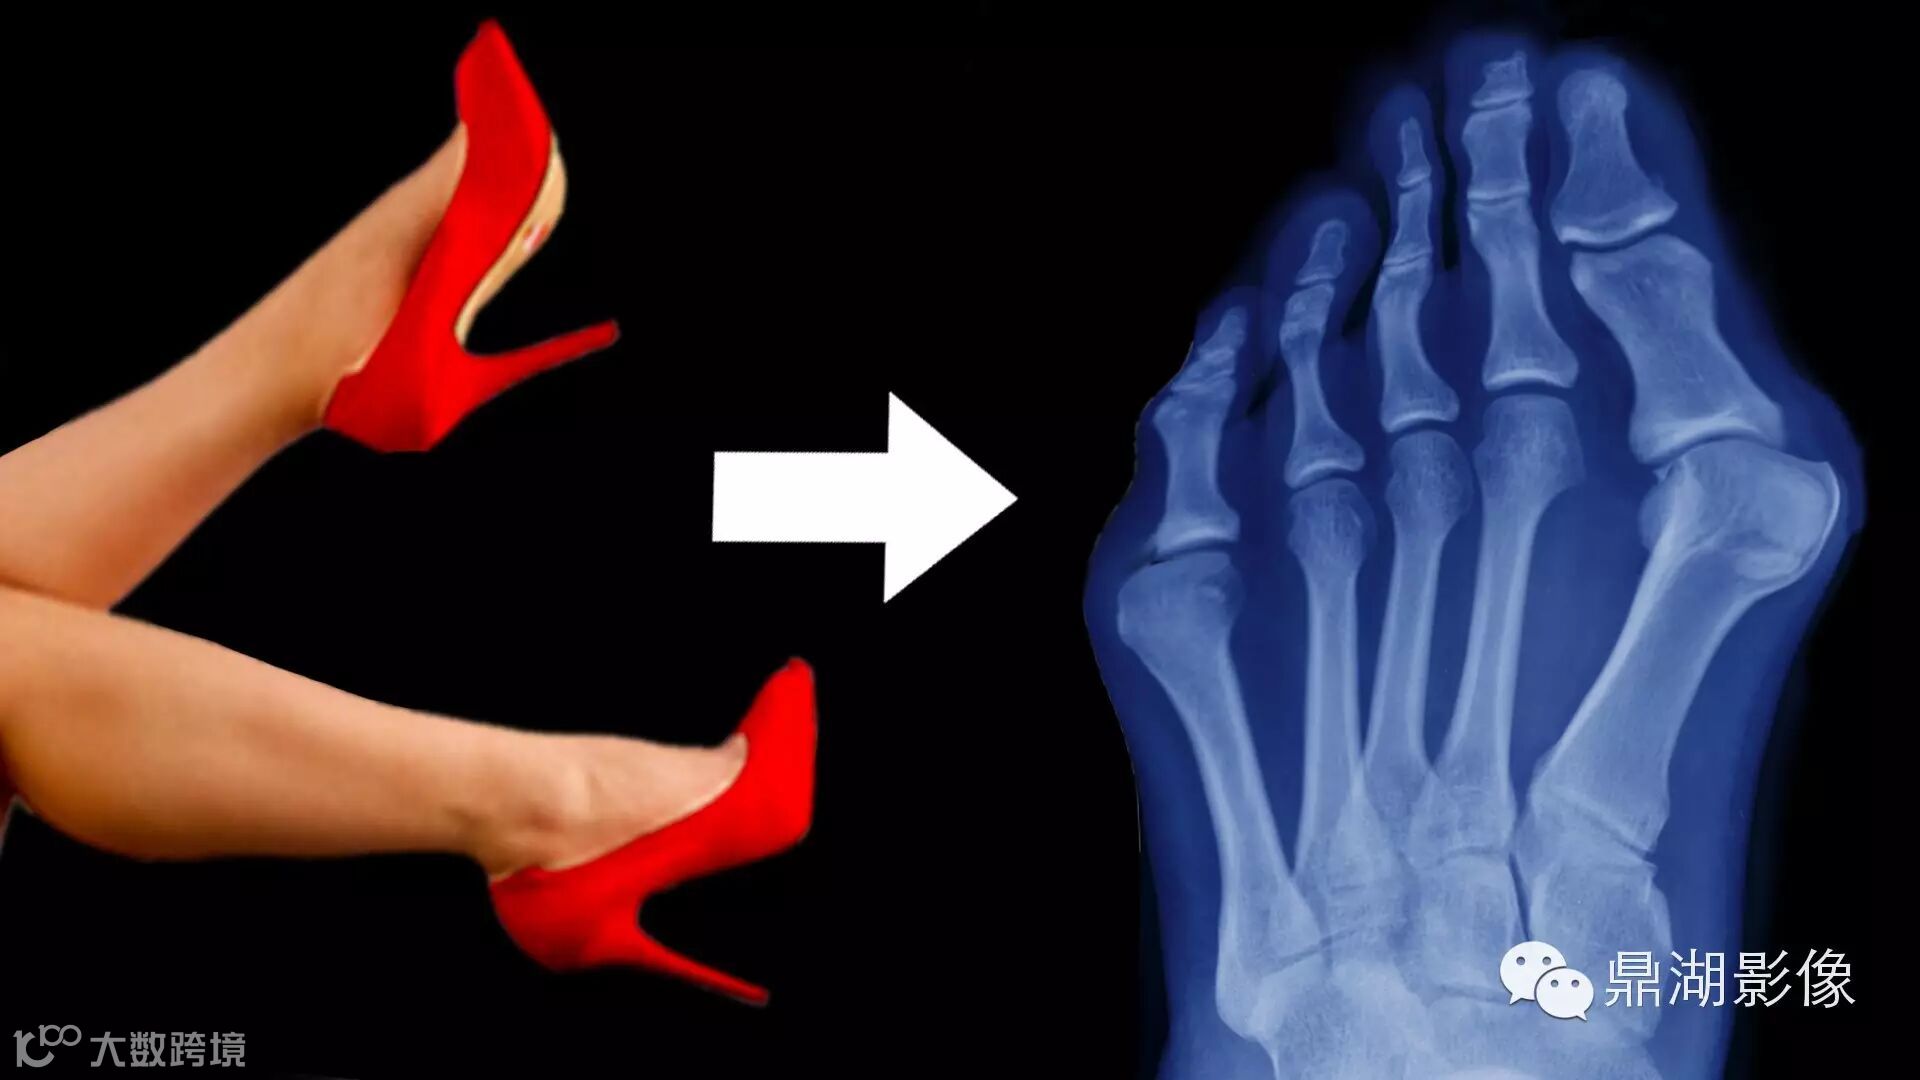

1拇外翻,锤状趾

足跟被抬高后,大部分的身体重量就落在前脚掌上。行走过程中,已经朝下的脚趾们会被重力慢慢挤进本就狭小的鞋尖。长期穿跟高头尖的鞋,大脚趾就被迫向二脚趾靠拢,于是二脚趾只能委曲求全尽量弓起身体,把前面的空间让给老大。久而久之,脚趾的骨骼就适应这种变化了。等它们承受不住开始疼痛时,你才知道大脚趾拇外翻了,二脚趾也锤状趾了。

2拇囊炎

紧贴高跟鞋会让大拇指基底部关节骨质增生,引起疼痛,且迫使其他脚趾的方向扭曲。